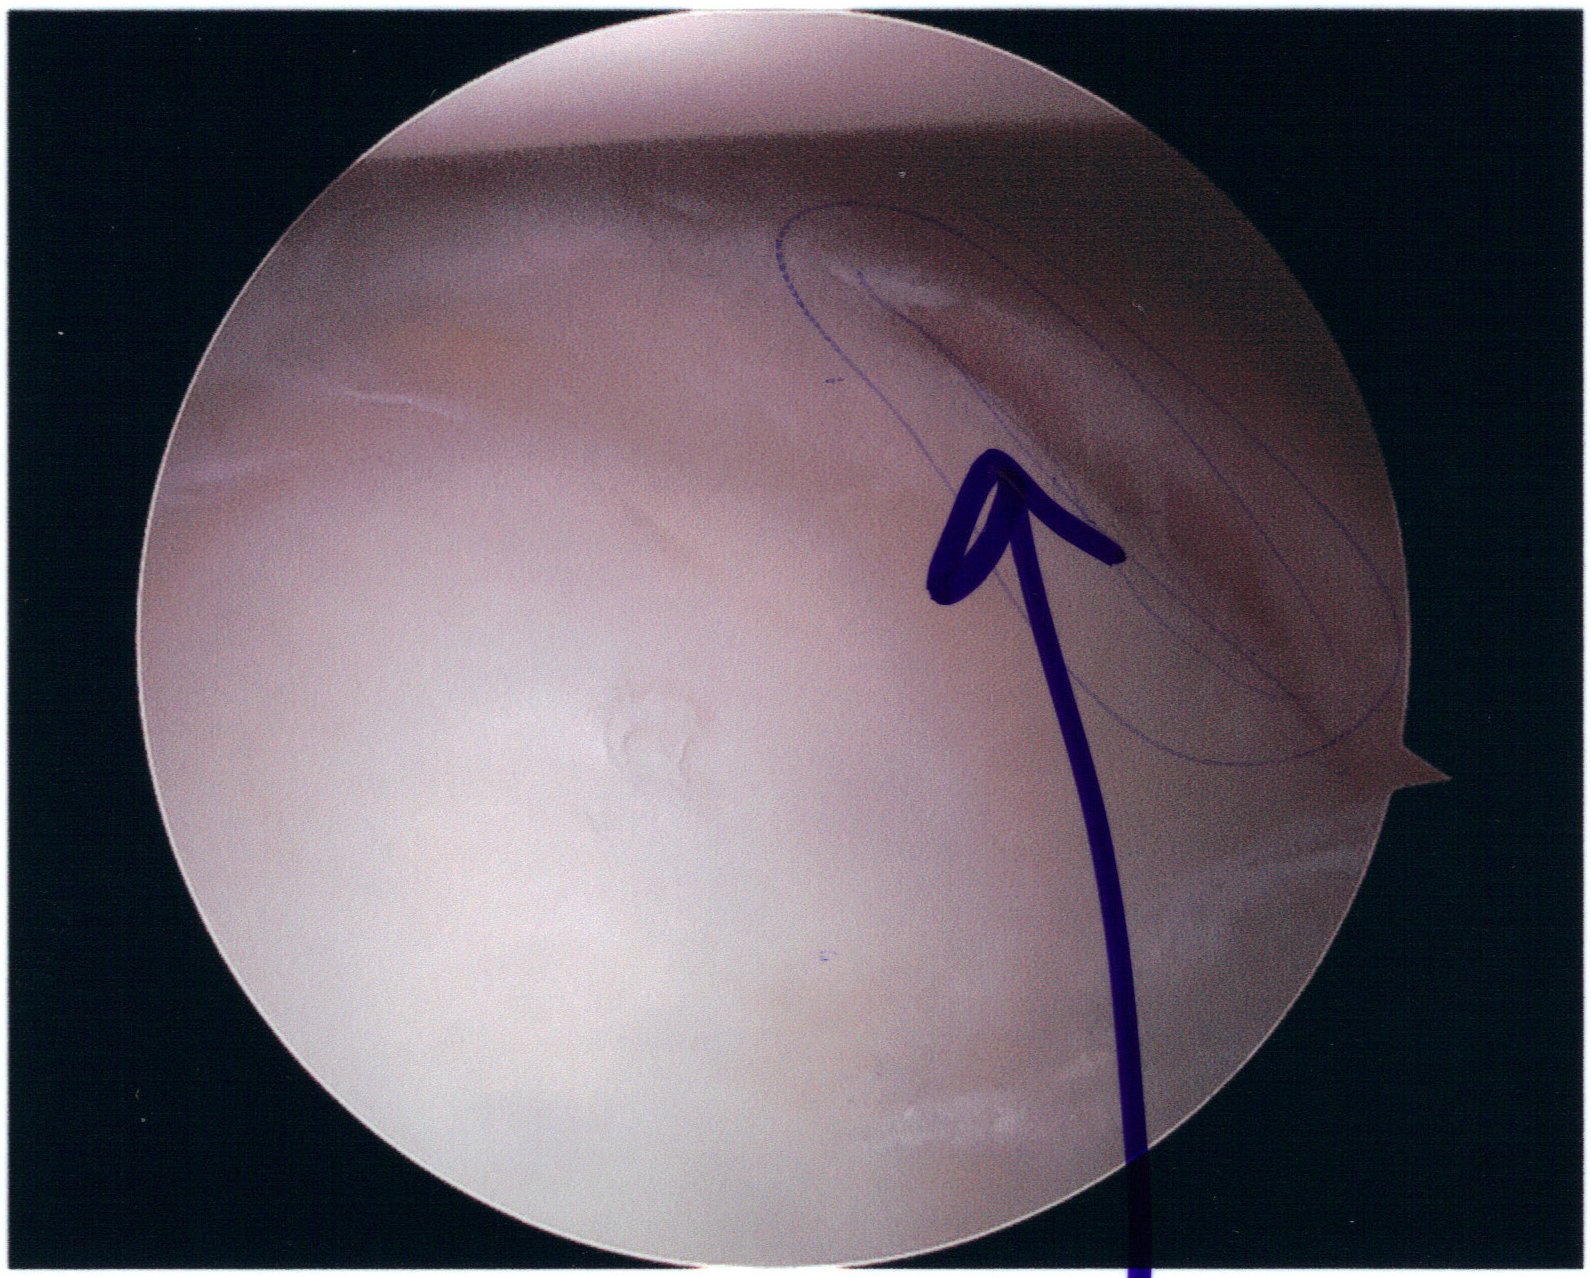

Glenoid labrum: A fibrocartilaginous ring that deepens the glenoid cavity. The anteroinferior labrum is the most common site of Bankart lesions. Note normal superior labral variants: Buford complex and sublabral foramen.

| Bankart | Anterior | Anteroinferior glenoid rim fracture (osseous Bankart) or labral tear (soft Bankart) | CT: osseous fragment; MRI arthrogram: labral tear; >20–25% glenoid width = significant bone loss |

| Reverse Bankart | Posterior | Posteroinferior glenoid rim fracture or posterior labral tear | CT or MRI arthrogram |